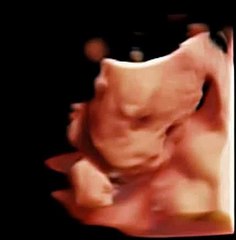

Q5 by Chison imaging Fetal Heart sonogram, easy to see heart in fetus, neonatal ultrasound